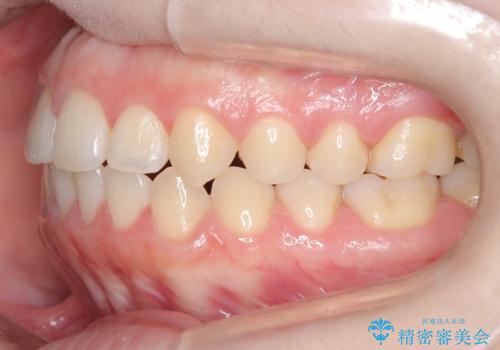

前歯のガタツキ、前歯の噛み合わせ(開咬)をインビザライン治療で治しました

- 前歯のがたつき、噛み合わせが気になるとのことで来院された患者様です。

インビザラインを使用して治療しました。

前歯がしっかり噛んでない状態(開咬)を治すために、前歯にゴムをかける必要があります。ゴムかけは患者様にご協力していただきます。